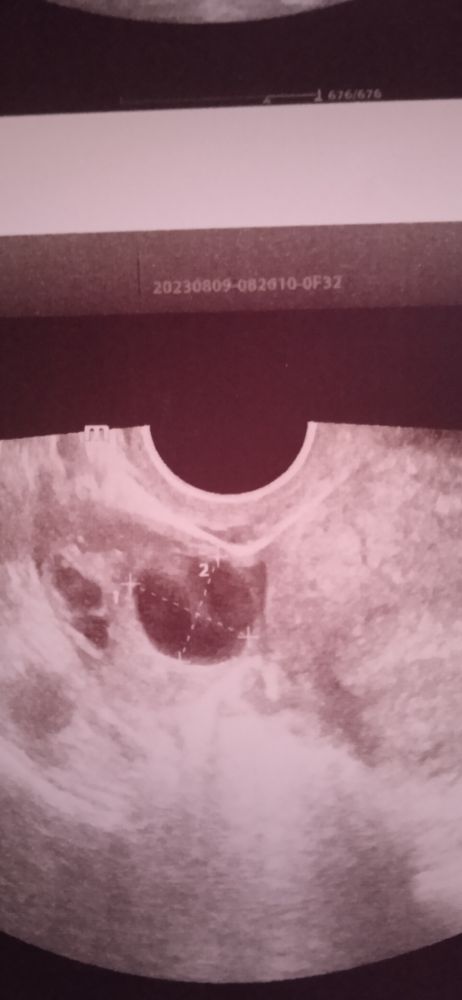

Делала в разных местах, ну какая же это киста😭, на УЗИ было сказано доминант, подтекает, а написала совсем другое.. Кто-нибудь сталкивался с таким??

У вас овуляция. Многие врачи пишут и на фолик и на желтое тело-функциональная киста. Как по мне, так от безграмотности, может и принято так у них)))

Ирина Герасимова, спасибо большое, прям плачу сижу. Я этот доминант долго ждала❤😭. Я точно слышала фолликул, доминант, вокруг жидкость, подтекает что ли. Скорее всего преобразовывается в жт. А заключение вынесла совсем другое. Спасибо Вам большое за ответ.

Урашка, да, я сегодня щитовидной железы делала и заодно посмотреть решила фолликул, вчера сильная острая боль в течении двух часов длилась. Я думаю может она по запарке так написала. С щитовидной чего то намудрила. Она ясно сказала фолликул, подтекает, возможно идёт овуляция именно сейчас. Жидкость рядом с фолликулом.